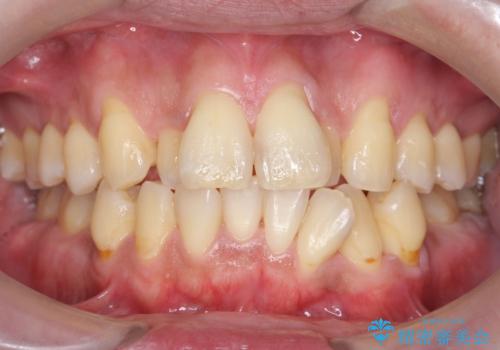

前歯の虫歯 矯正治療してからしっかり治す

- 前歯の重なったところが虫歯になり、物理的にアプローチが難しい状態でした。

矯正治療前に虫歯を取り、歯並びが良くなってから本格的にセラミック治療を行いました。